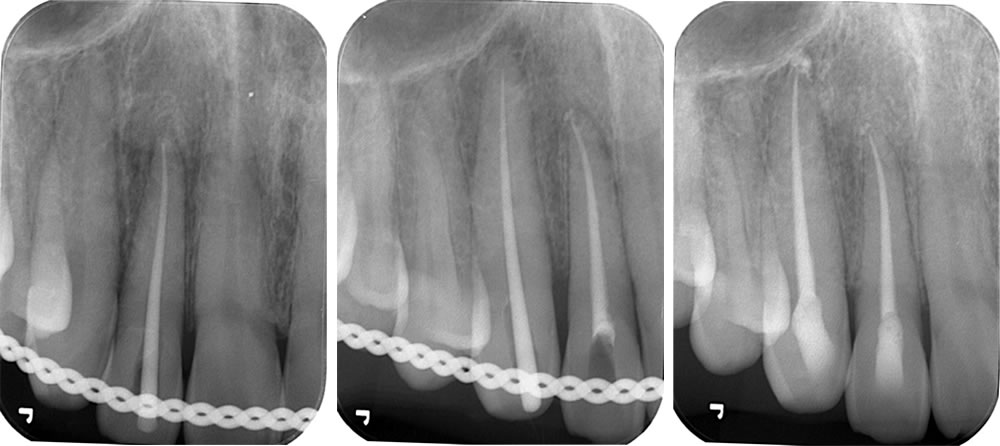

術後2年後の経過観察

術後経過2年の口腔内写真です。歯の変色もなく、機能面、審美面ともに経過良好でした。

こちらはレントゲンとCT画像になります。受傷後は骨から大きく飛び出ていた歯牙は正しい位置にあります。また、正常な歯根膜の確認もでき、経過良好です。